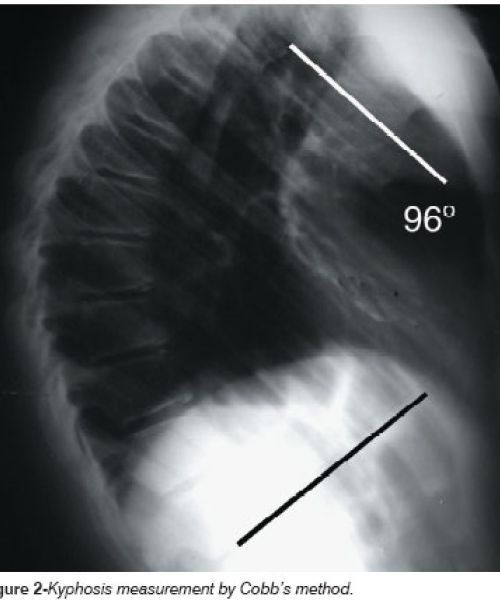

Κύφωση

Είναι η υπερβολική κυρτότητα της θωρακικής μοίρας της σπονδυλικής στήλης. Η πάθηση προσβάλλει συνήθως αγόρια εφηβικής ηλικίας και η αιτία εμφάνισης είναι ιδιοπαθής.

Η θεραπεία περιλαμβάνει  κινησιοθεραπεία, προσοχή στάσης και θέσης ακόμα και στον ύπνο ενώ σε περιπτώσεις που η κυρτότητα είναι μεγαλύτερη των 40º, συνίσταται η χρήση ειδικού κηδεμόνα